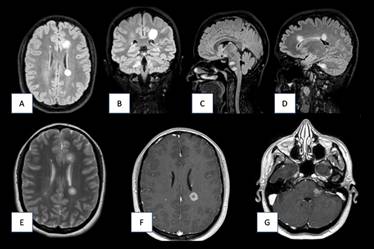

Los estudios radiológicos ponen de manifiesto a nivel encefálico la existencia múltiples lesiones de hiperseñal localizadas a nivel de sustancia blanca bilateral con afectación de la intersección cortico-subcortical, así como lesiones infratentoriales que afectan a troncoencéfalo, bulbo, pedúnculos cerebelosos medios bilaterales y a hemisferio cerebeloso derecho (Figura 1). Dichas lesiones presentan -tras la administración de contraste paramagnético- diversas áreas de realce irregular por el mismo (Figura 2).

Figura 1 RM cerebral en los tres planos del espacio en diferentes secuencias al momento del diagnóstico. A y B) RM cerebral corte axial (A) y sagital (B) secuencia FLAIR. Se objetiva hiperintensidades nodulares en la sustancia blanca periventricular. C y D) RM cerebral corte sagital secuencia FLAIR. Afectación a nivel del troncoencéfalo (C) con presencia de dos lesiones ovoideas marcadamente hiperintensas, que también son visibles en cuerpo calloso y cerebelo (D). E) RM cerebral corte axial T2. Se objetiva hiperintensidades nodulares en la sustancia blanca periventricular. F y G) RM axial con contraste paramagnético, donde se evidencia captación de contraste de manera periférica de las lesiones antes descritas.